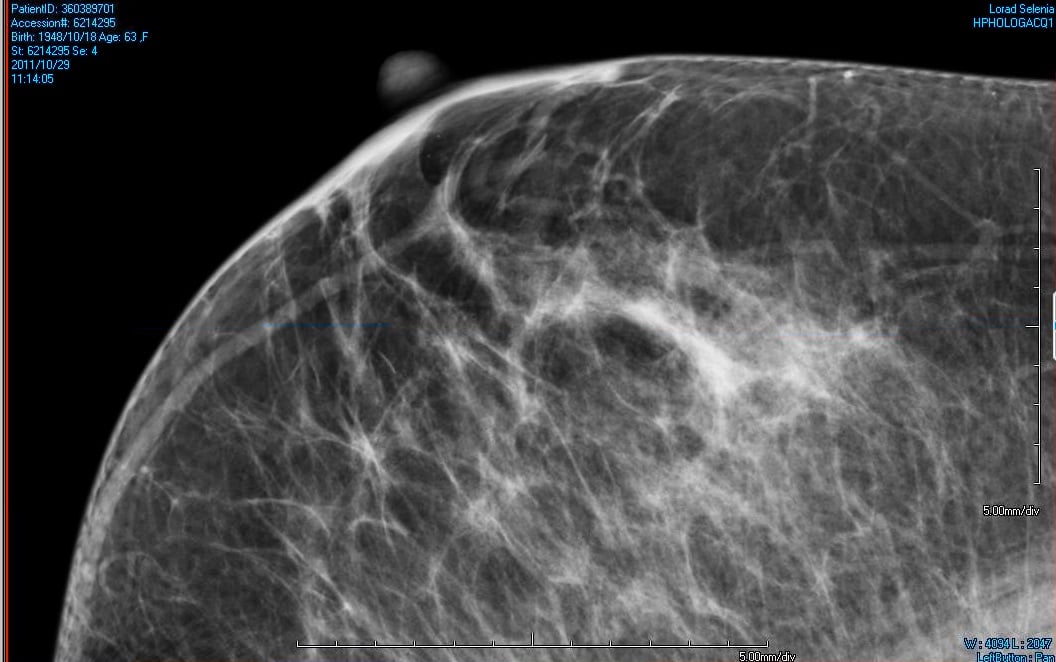

Mammogram Images Normal And Abnormal from www.verywellhealth.com Any area that does not look like normal tissue is a possible cause for concern. Dense breast tissue appears solid. A diagnostic mammogram is used to check for breast cancer when there is a sign or symptom of disease. They are not usually related to cancer. Your doctor will note if they have changed over time. If you've had a mammogram before, the radiologist should compare your old mammogram to the new one to look for changes. A lump or tumor will show up as a focused white area on a mammogram. It can be hard to know from a mammogram image whether the cluster is dcis or invasive breast cancer.

The first stage of breast cancer detection is the mammogram, ultrasound or breast magnetic resonance imaging exam, all of which are sensitive enough to detect breast cancer before any symptoms are noticeable.if there are any suspicious signs, then a biopsy is carried out, and only then are tests for breast. It is also an anatomic test, which means cancer is detected based on changes in how the breast anatomy looks. Fluid is black on an ultrasound. The most common sign of breast cancer is a lump, deep in the breast. Mammograms may show suspicious areas of the breast, white spots, and microcalcifications. Ultrasounds are useful for detecting signs of breast cancer even after a mammogram comes back negative. Your doctor will note if they have changed over time. • microcalcifications are small and may appear in clusters. Lobular carcinoma) are more difficult to detect than. It can be hard to know from a mammogram image whether the cluster is dcis or invasive breast cancer. You can tell they are solid due to their grey color. Tumors may be benign or cancerous. Rather than an image that is formed from pictures taken from top to bottom and side to side like a.

While it is useful to know what cysts and tumors look like in an ultrasound image, always rely on the insight of an experienced doctor or radiologist when. The look of breast cancer on a mammogram a tumor or lump will appear as a focused white area on the mammogram. The photographs included on this page are the results of reconstructive procedures performed by the surgeons at the center for restorative breast surgery. Any area that does not look like normal tissue is a possible cause for concern. A mammogram can show breast changes such as calcifications, masses, or other symptoms that might be cancer. During a breast exam, your doctor looks for visual changes and uses their fingers to feel for lumps. They are usually benign (not cancer). Inflammatory breast cancer affects breast tissue and can appear unusually dimpled or thick. • microcalcifications are small and may appear in clusters. Dulce corazon the transfer of estrogen from a mother to her newborn child may cause breast lesions on the child. Most people assume that what doctors are looking for on a mammogram are lumps, dr. The doctor reading your mammogram will be looking for different types of breast changes, such as small white spots called calcifications, larger abnormal areas called masses, and other suspicious areas that could be signs of cancer. The following images show what cancer looks like on an ultrasound.

Tmist Trial Comparing Breast Cancer Screening Approaches National Cancer Institute from www.cancer.gov These deposits show up as tiny white spots on a mammogram, and there may be only one or two, or too many to count, says jay baker, md, a breast imaging specialist at the duke cancer center. It is also an anatomic test, which means cancer is detected based on changes in how the breast anatomy looks. You may have an imaging test, like a mammogram or ultrasound, for an inside look. A lump is not always easy to feel. Fluid is black on an ultrasound. Dulce corazon the transfer of estrogen from a mother to her newborn child may cause breast lesions on the child. A screening mammogram is performed at regular intervals to check for breast cancer in women who have no signs or symptoms of the disease. Breast cancer can appear as a spiculated mass, cluster of tiny calcifications, smoothly marginated mass, area of subtle distortion or be invisible on.

Generally speaking, the denser the tissue, the whiter it appears. The harmless nature of ultrasound machines also make them a benefit to patients. Mammograms may show suspicious areas of the breast, white spots, and microcalcifications. Lobular carcinoma) are more difficult to detect than. While it is useful to know what cysts and tumors look like in an ultrasound image, always rely on the insight of an experienced doctor or radiologist when. People should become familiar with the typical look and feel of their. (a cluster of microcalcifications can also be a benign finding on a mammogram. Most people assume that what doctors are looking for on a mammogram are lumps, dr. There are few risks associated with mammography. You can tell they are solid due to their grey color. On the body, a lesion is an area with is an abnormality or alteration in the tissue's integrity. According to the american cancer society (acs), the most common sign of breast cancer is a new lump or mass in the breast. This has an odd shape and grey color.